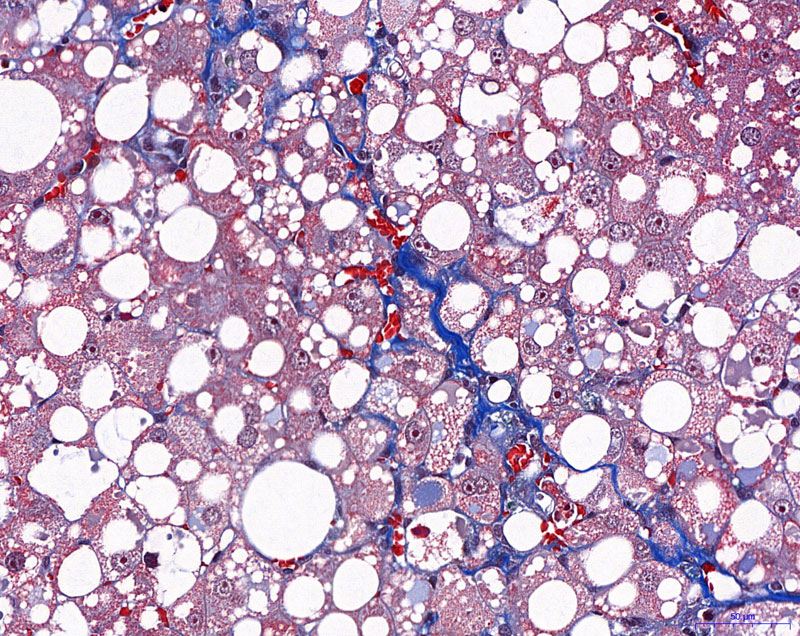

MASSON染色【組織病理染色】

給藥組-400

模型組-400

正常組-400